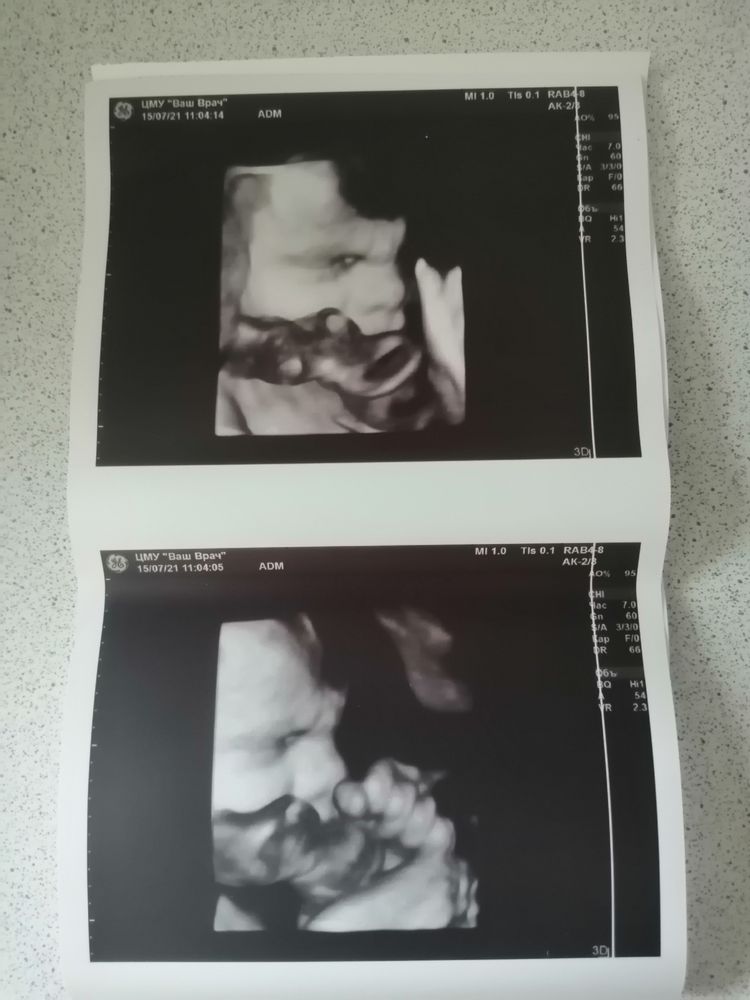

Посмотрела на своего бусика в 3d режиме щёчки и носик такие толстенький наел-морщился, улыбался, глотал водичку😍только стали фото печатать, дурацкая пуповина закрыла ротик🤷♀️